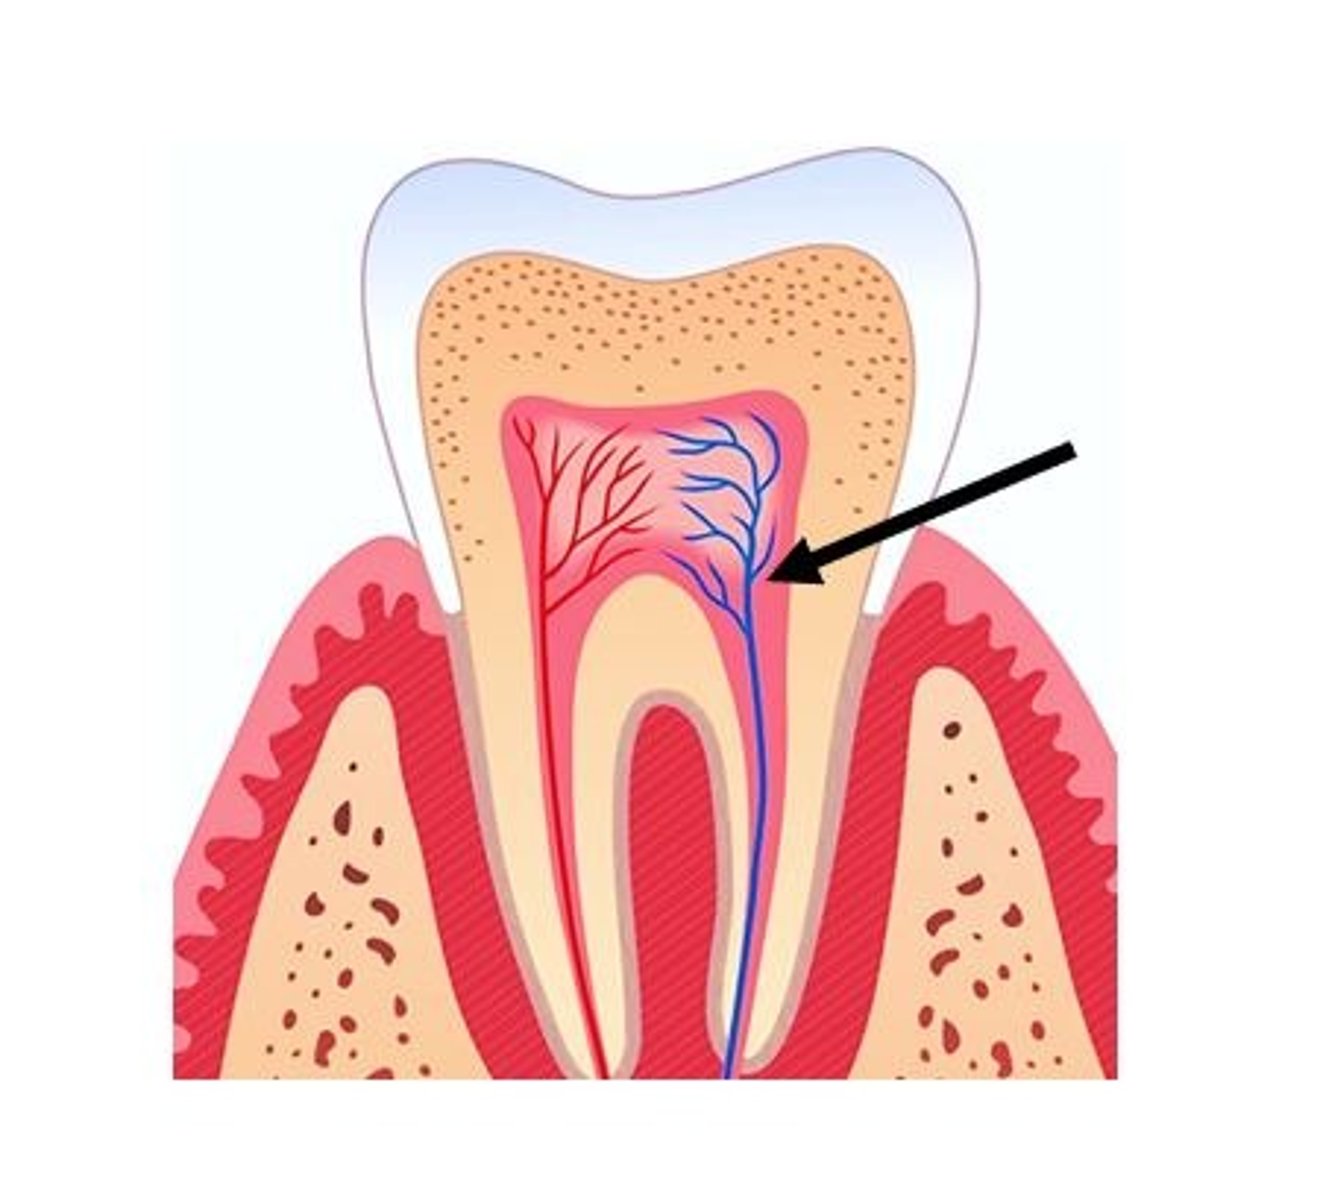

pulp

Which tooth tissue contains

<p>Which tooth tissue contains</p>